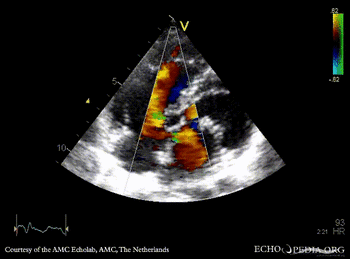

| Courtesy of: AMC Echolab, AMC, The Netherlands | |

| PSAX: Color Doppler, ASD type I | A4CH: Color Doppler ASD type I |